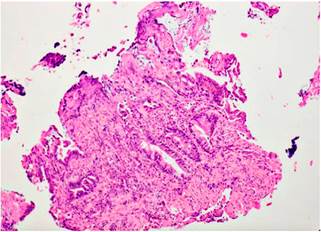

Ileocolonoscopy identified solitary rectal ulcer, with no lesions in the ileal mucosa. Histopathology samples from May 2016 were evaluated by institutional pathologists, in which mucosa with tissue artifacts was found with focal presence of cell groups with cytologic and architectural atypia (Figure 4), so adenocarcinoma was initially suspected based on the inflammatory reactive changes. However, the lesion was not represented in immunohistochemical sections. In the new samples obtained at our center, hyperplastic mucosa was found without dysplasia, as well as ulcer fragment without tumor lesions (Figure 5); no architectural changes, microorganisms, granulomas, or clear fibromuscular replacement of the lamina propria were observed.

Figure 4 Fibroinflammatory replacement of the lamina propria. Hematoxylin and eosin stain (H&E): 10 X.